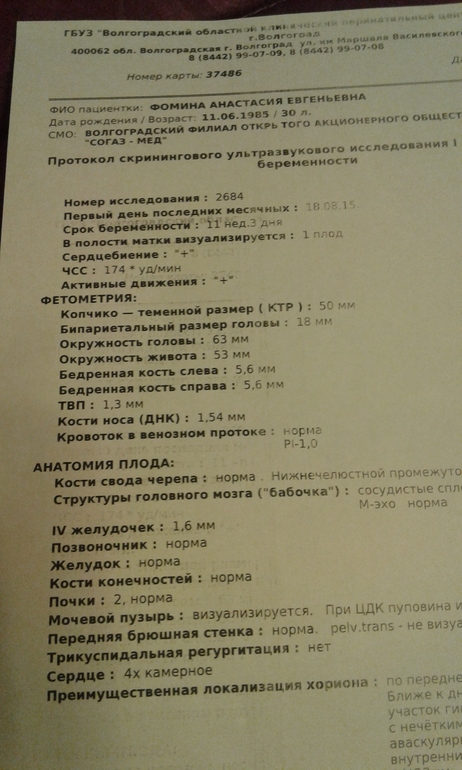

Получилось все очень неажиданно так сказать с корабля на бал😊😆😄 поехала с выпиской с эндокринологии сразу в перенатальный и мне сделали сразу скрининг....я так боялась..сидела в очереди и ттреслась как лист осины...но у нас все хорошо. Жду крови она будет во вторник.. ..

Наш первый скрининг...

Огогошечки) Вот он первый скрининг! Как много цифр) Малышик такой мииииленький! Лежит у мамки в животике) Настя, боже мой, вот оно счастье! Ну, первый триместр почти позади) Растите и дальше! Здоровья тебе и малышу!!!

Уже целый человек  5 см!!! Вот и первый скрининг пройден на ура- поздравляю. А те кто ноют после 3 го раза- пусть плачут так проще и легче, кто то и на 10 й раз стойко держится а кто то и с 1 го ломается...